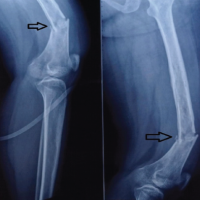

Case Report: We present a case of a 65-year-old male farmer who presented with swelling and persistent pain in the right foot, particularly over the third toe. The patient had a history of trivial trauma and previous incision and drainage for a foot swelling. Radiographic and magnetic resonance imaging findings indicated a well-defined lytic lesion with cortical thinning and breach over the third metatarsal, raising suspicion for tuberculous osteomyelitis. Surgical exploration revealed an encapsulated cyst filled with cheesy material. No sequestrated bone or osteomyelitis was found.

A 65-year-old male farmer presented to the outpatient department with complaints of swelling and persistent pain in the right foot, particularly over the third toe. The patient had been experiencing localized swelling and pain for the past 4–6 weeks, which did not subside despite treatment with antibiotics and analgesics prescribed by his local practitioner. The patient, a farmer by profession, lives with his spouse in a rural setting. His occupation, which involves significant physical activity, including walking, standing, and heavy lifting, likely contributed to the stress on his feet. He has no significant history of smoking or alcohol use. The patient reported a prior history of minor trauma to the right foot 5 years ago, which was managed conservatively with no long-term complications. Two years ago, the patient experienced similar swelling in the same foot, for which an incision and drainage procedure was performed at an outside hospital. Still, there were no subsequent issues after the procedure. At the time of presentation, the patient denied any systemic symptoms such as fever, weight loss, or malaise. He also reported no history of chronic conditions like diabetes, hypertension, or autoimmune disorders. The patient was not taking any long-term medications except for those prescribed for pain and swelling during the current episode. He had no prior history of significant illnesses or surgeries other than the previous minor trauma and surgical intervention on his right foot (Fig. 1-7).